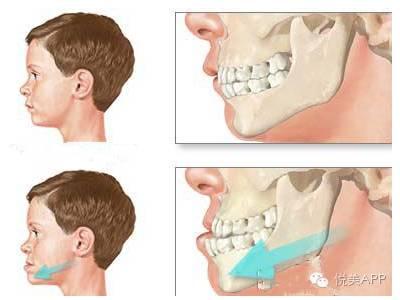

地包天:下牙咬到上牙的外面,即俗称地包天、月亮脸,除了丑,还会造成咀嚼,发音等障碍。

地包天医学名称为反颌,分为骨性与牙性,牙性普通正畸即可,骨性的需要结合正颌外科手术。

成人严重的地包天~

霸气彪悍的地包天~

这是一个已经介入治疗的小男孩,通过比对能看出已经矫治不少~

早期的少儿矫治,采用外力加压~

第二步:正颌外科手术,将长出来的部分骨头切除,然后往回推,固定住,形成正确咬合状态~

第一种:下颌骨矫正——将下颌骨截骨,去除一段,整体后退,固定,不但缩短下颌的长度,而且在后退的同时伴有上颌骨向上旋转,下颌角的角度变小,侧面也更好看,如果下巴颏太长,还可以缩短。

悦大咖放一个下颌支矢状骨劈开术,大家不要害怕(看懂示意图就可以了)~